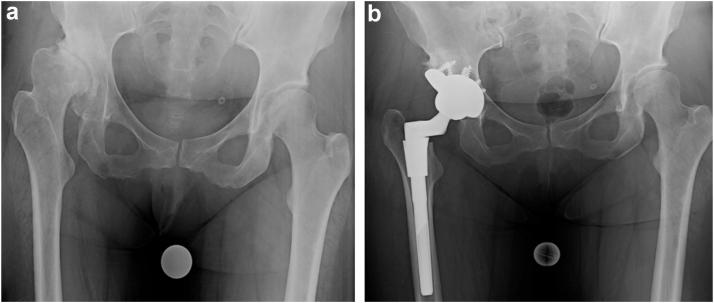

Trabecular metal augments (TMAs) have been extensively used in revision total hip arthroplasty (THA) to address acetabular bone defects. However, limited data exists regarding TMA utilization during primary THA. This study aims to assess the clinical and radiographic outcomes of TMAs used during primary THA.

Twenty-six patients (30 hips) were included with average age of 52.6 ± 15.3 years (range: 22-78) and mean follow-up of 4.1 ± 2.1 years (range: 2.0-8.9). Most TMAs were indicated for developmental dysplasia of the hip (n = 18; 60.0%). On average, hip center of rotation was lowered 1.5 ± 1.3 cm and lateralized 1.2 ± 1.5 cm, while leg length and global offset were increased by 2.4 ± 1.2 cm and 0.4 ± 1.0 cm, respectively. At final follow-up, 3 hips (10.0%) required revision: one (3.3%) for aseptic loosening and 2 (6.7%) for instability. No patients had progressive radiolucent lines at final follow-up. Five-year survival with aseptic loosening and all-cause revision as endpoints was 100% (95% confidence interval: 90.0%-100.0%) and 92.1% (95% confidence interval: 81.3%-100.0%), respectively. One patient required revision for aseptic loosening after the 5-year mark.

小梁金属增强物(TMA)已广泛应用于翻修全髋关节置换术(THA)以处理髋臼骨缺损。然而,关于初次THA期间TMA使用的数据有限。本研究旨在评估初次THA期间使用TMA的临床和影像学结果。

纳入26例患者(30髋),平均年龄52.6±15.3岁(范围:22 - 78岁),平均随访4.1±2.1年(范围:2.0 - 8.9年)。大多数TMA用于髋关节发育不良(n = 18;60.0%)。平均而言,髋关节旋转中心降低1.5±1.3 cm,向外移位1.2±1.5 cm,而肢体长度和整体偏移分别增加2.4±1.2 cm和0.4±1.0 cm。在末次随访时,3髋(10.0%)需要翻修:1髋(3.3%)因无菌性松动,2髋(6.7%)因不稳定。在末次随访时,没有患者出现进展性透亮线。以无菌性松动和全因翻修为终点的5年生存率分别为100%(95%置信区间:90.0% - 100.0%)和92.1%(95%置信区间:81.3% - 100.0%)。1例患者在5年标记之后因无菌性松动需要翻修。